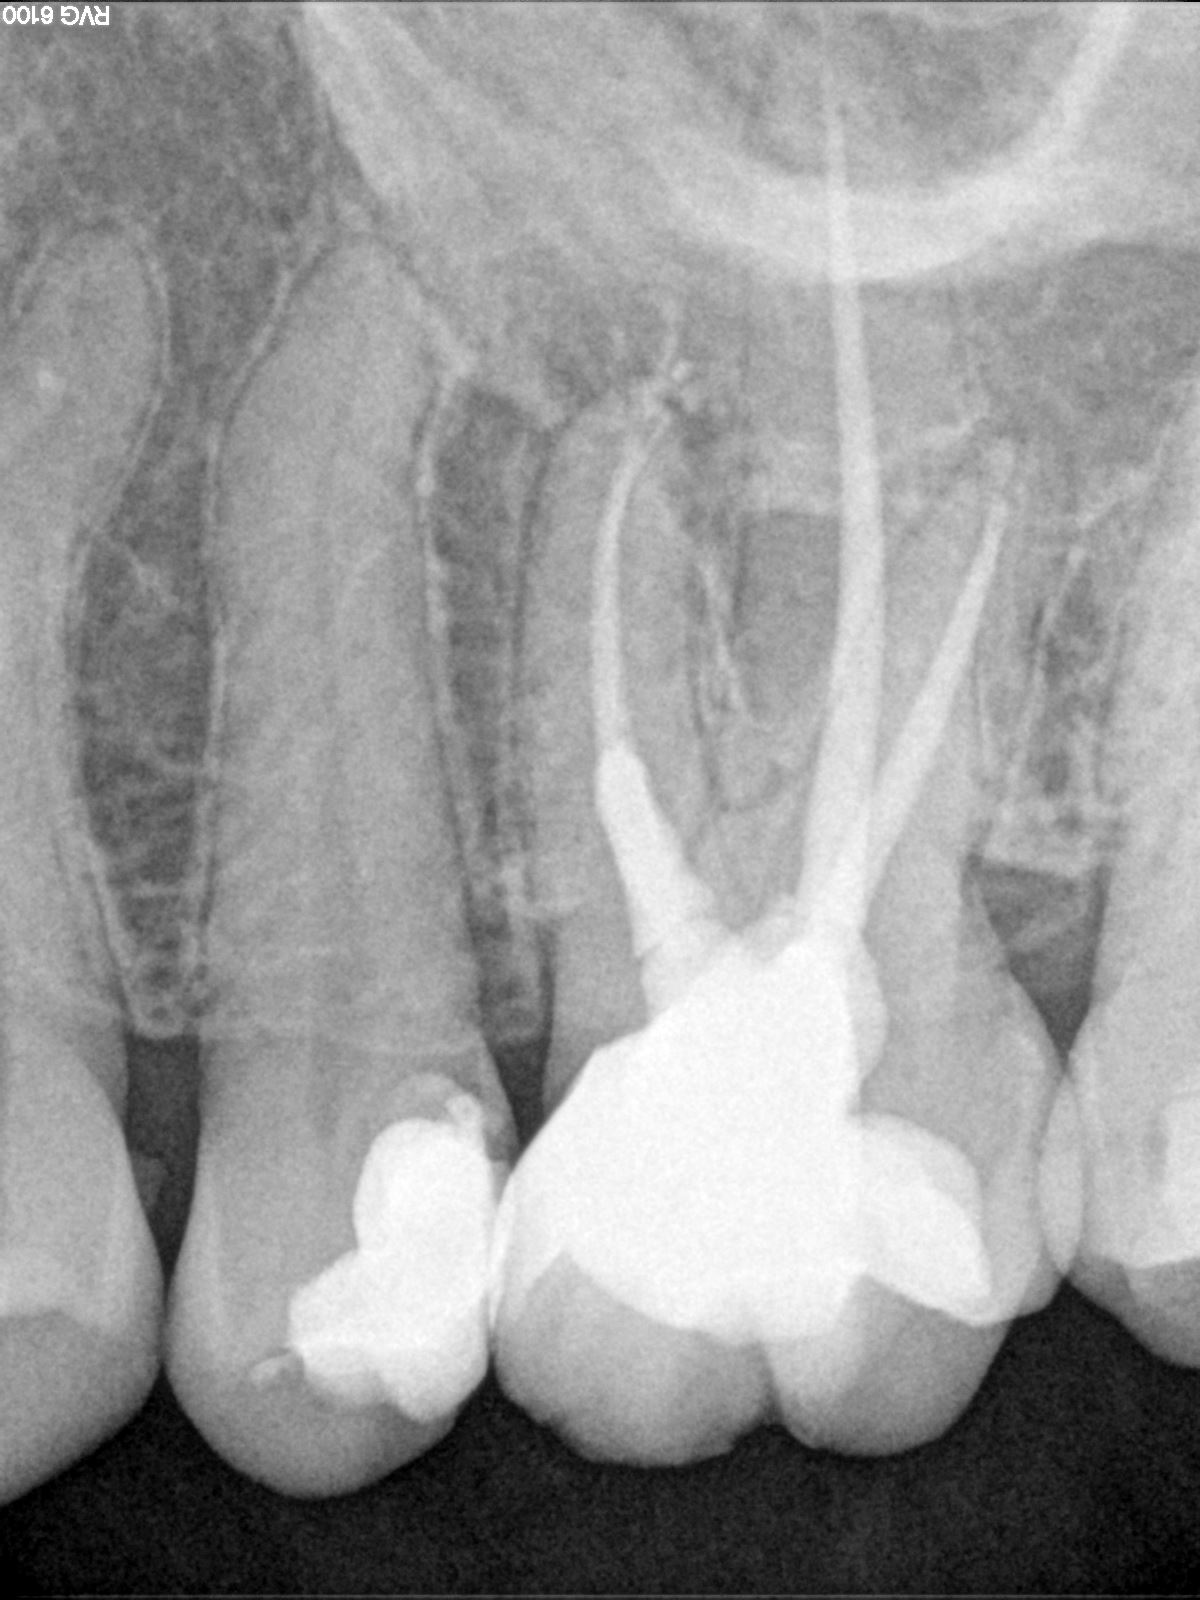

Obturation :

Les cônes de guttas correspondants sont sélectionnés et le scellement à l’aide d’un ciment biocéramique (Ceraseal) est appliqué dans le canal à l'aide d'un lentulo. Les cônes de gutta sont ensuite coupés à l’entrée des canaux.

Le nouveau système Procodile Q de Komet permet une préparation canalaire très efficace avec un minimum de limes. Cela permet de travailler plus rapidement. Le mouvement alternatif entraîne moins de risque de casse et le nombre limité de limes réduit également le coût du matériel. Le scellement biocéramique permet d'utiliser la technique du cône unique. Cette technique est plus rapide et plus facile à réaliser. En résumé, la combinaison des limes Procodile Q avec le scellement biocéramique Ceraseal garantit un traitement canalaire rapide, simple et prévisible.